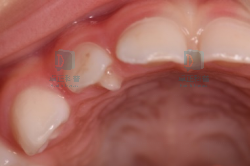

E牙专属:多长了一个尖?

有些牙齿性格比较“E”,由于个性太张扬,以至于发育的时候比正常牙齿多出了一个牙尖,门牙比较常见的是畸形舌侧尖,后牙则是畸形中央尖。

1

畸形舌尖;

图片

多见于乳牙或恒牙的门牙,表现为牙齿形态呈“T”型,发现畸形舌尖建议由医生评估是否妨碍咬合,若妨碍咬合或牙尖折断则需要由医生处理